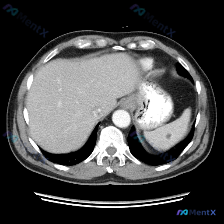

今天看到一个挺有警示意义的影像读片场景,整理一下思路: 初始问题与预设 用户直接问:「这个图像里的脾脏病变是什么异常?」 预设非常明确:先认定了存在脾脏病变,让我们找出来并定性。 影像事实(基于提供的单层面上腹部CT软组织窗横断面 1. 扫描范围:上腹部较高层面,显示部分肝脏、脾脏、腹主动脉等结构...

今天看到一份挺有意思的影像分析案例,不是典型的“看图识病”,而是反过来——预设了“病变”,但图里没找到。 先把情况理一理: --- 病例背景 - 焦点问题:图像中识别出的异常是什么?脾脏病变 - 影像资料:单张腹部CT横断面,软组织窗,增强扫描(门脉期/平衡期左右) 影像核心表现(客观整理) 这份图...

整理了一个很有意思的影像分析案例,切入点和平时不太一样——这次不是找病变,而是“排除”一个预设的病变。 --- 先看基本影像背景 这是一张腹部CT轴位软组织窗的单张图像。 影像核心描述整理: 1. 肝脏:轮廓平滑,密度均匀,血管走行正常,未见占位。 2. 脾脏(焦点):形态清晰,大小正常,脾实质密度...

看到一个病例资料挺有意思,整理了一下思路和大家讨论。 用户最初的问题是“图中观察到的特定异常是什么?脾脏病变”,等于先给了一个“存在脾脏病变”的前提。但拿到这张上腹部CT横断面图像(倾向于增强扫描的动脉期或门脉期),仔细看下来,情况其实不太一样。 --- 先看影像层面的客观发现: - 扫描质量与层面...

看到一个资料,问题直接指向「脾脏病变」,附上了一张腹部增强CT的横断面图像。整理一下读片和分析思路,这个病例的核心其实不是「找病变」,而是「怎么面对阴性结果」。 病例影像基础信息 - 检查手段:腹部CT横断面,软组织窗 - 增强状态:根据血管及实质强化,考虑为静脉期/平衡期 - 扫描层面:上腹部,包...